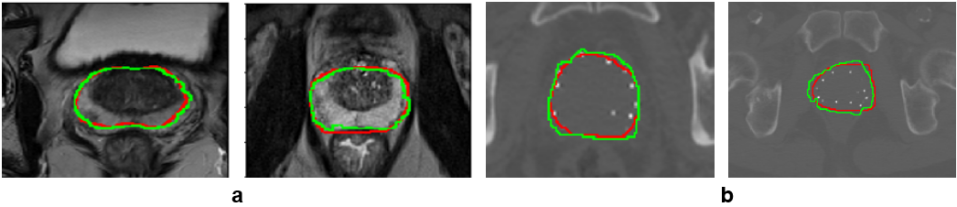

Automatic segmentation of anatomical structures in medical images has various medical applications. For example, in radiotherapy prostate segmentation is essential in the diagnosis, therapy, and post-therapy analysis of prostate cancer. It is critical in selecting patients for a specific treatment, to guide source delivery and in computing dose distribution [1, 2]. T2-weighted MRI is the modality of choice for prostate segmentation. However, CT and US are also routinely used because: 1) CT image is used to calculate the dose distribution due to its characteristics of relating the density of tissues with the voxel intensity, and 2) US imaging is suitable for real-time image guided radiotherapy. Despite the need for accurate segmentation of the prostate in radiotherapy, manual segmentation is subjective to inter and intra-observer variabilities, time-consuming, and depends on the experience of the physician. Automatic and reliable segmentation of the prostate on these images is thus an important but difficult task due to the inhomogeneous and inconsistent contrast of prostate boundary and large shape variations. This is particularly complicated on CT images because of the inherent low-contrast imaging characteristics of CT for soft tissues (such as prostate boundary) as can be seen from Fig. 1 (b).

Figure 1: Prostate image examples showing image contrast variations in: (a) T2-weighted MRI, and (b) CT images with seeds from low-dose-rate brachytherapy.

The generator was trained using a five-fold cross validation method using T2-weighted MRI. It was then kept as a shape predictor by freezing its weights during training of the proposed method. As this is an intermediate output of the method, it can be considered as a region proposal (or as instantaneous shape generator) to be further refined by merging with the encoder-decoder output. Indeed, the model-generator can learn from good contrast images (MRI) and used directly (transfer without fine tuning by freezing) for low contrast images (CT), while the encoder-decoder extracts additional features. As one can see from the qualitative prostate segmentation results in Fig. 3, the proposed method can segment accurately the prostate on both T2-weighted MR and CT images.

Figure 3: Qualitative evaluation of prostate segmentation on 2D: (a) T2-weighted MRI, and (b) CT images with seeds from low-dose-rate brachytherapy. The ground truth labels are shown in red and segmentation results in green.

In almost all evaluation metrics (with and without the generator, Table 1), the proposed method with the shape model generator outperforms the state of the art methods. Since the implanted radioactive seeds were not uniformly placed over the volume of the prostate gland, it was observed to influence the segmentation quality (particularly the state of the art methods). However, they might perform better on CT images without the implanted radioactive seeds. Combining CNN-based extracted features with prior shape knowledge of the organ can improve time, reproducibility, and accuracy in fully automatic segmentation of the prostate in radiotherapy.